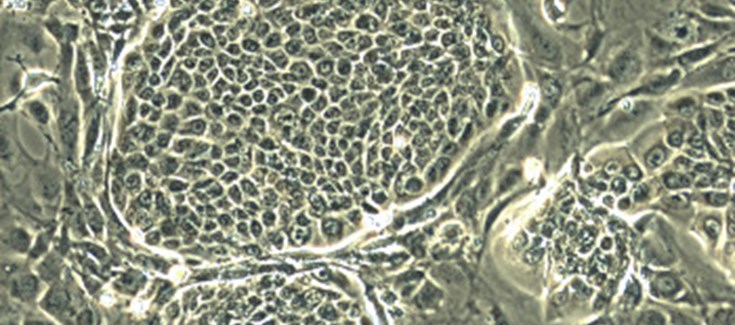

Colonias de células epidérmicas editadas genéticamente

Un trabajo de la U714 CIBERER en el CIEMAT-UC3M publicado en la prestigiosa revista Molecular Therapy ha demostrado por primera vez la capacidad regeneradora de piel de un único clon de queratinocitos humanos (células epiteliales de la piel) editado genéticamente. Aunque el clon provenía en este estudio de células normales y su edición génica las hacía expresar un gen marcador no terapéutico, el trabajo abre las puertas a otros en los que se corrija una enfermedad genética como la epidermolisis bullosa o enfermedad de piel de mariposa de forma segura evitando el riesgo de efectos adversos asociado a las estrategias de terapia génica tradicionales.